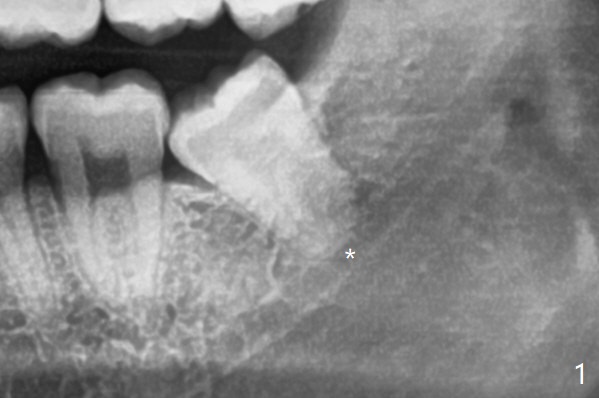

下牙槽神经管(*)位于智齿根尖下方(图一);一种拔除智齿方法是颊侧沟形成后,尽量松动智齿,包括牙根,在牙根周围形成空间(图二:黑色)